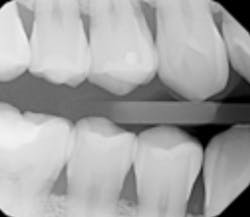

The selection of radiographic images can sometimes change depending on patient conditions, which appears to be the case here. It seems on a first new patient visit, only D0274 bitewing, four radiographic images appeared to be necessary. When the patient returned, it was determined the rest of the D0210 intraoral full series radiographic images were needed. Knowing the specific code's nomenclature/name is the first best step to understanding.

The second step is understanding the D0274 description, which reads, “A radiographic survey of the whole mouth, which usually consists of 14 to 22 periapical and posterior bitewing images intended to display the crowns and roots of all teeth, periapical areas, and alveolar bone.”

This means the bitewings are part of the full series. From a coding and documentation perspective, there are two separate dates of service. Each encounter should be listed for accuracy. For the second date when the full series is documented, a note should be added to the patient record with the date of the bitewings.